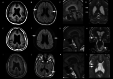

Methods: We reviewed the medical records of three siblings with BFPP including one elder girl and two identical twin boys from birth to adulthood. The clinical symptoms, electroencephalography (EEG), brain MRI, whole-exome sequencing, treatment including medications, neuromodulation, and epilepsy surgery, and clinical outcomes were reviewed. The protein structure of a novel missense variant (p.Leu290Pro) was predicted by in silico studies, and molecular analysis was performed via typical flow cytometry and Western blotting.

Results: The elder girl (Patient 1) was 22 years old and the twin boys (Patients 2 and 3) were 20 years old at the time of publication. All of them presented with typical clinical symptoms/signs and MRI findings of BFPP. Whole-exome sequencing followed by Sanger confirmation showed that all three patients had compound heterozygous variants in the ADGRG1 gene. The missense variant (p.Leu290Pro) was confirmed to be related to a reduction in cell surface GPR56 expression. High-amplitude rhythmic activity was noted in sleep EEG during infancy, which may have been due to excessive sleep spindle, and the rhythm disappeared when they were of pre-school age. Partial callosotomy provided short-term benefits in seizure control in Patients 1 and 2, and combined vagus nerve stimulation and partial callosotomy provided longer benefits in Patient 3.